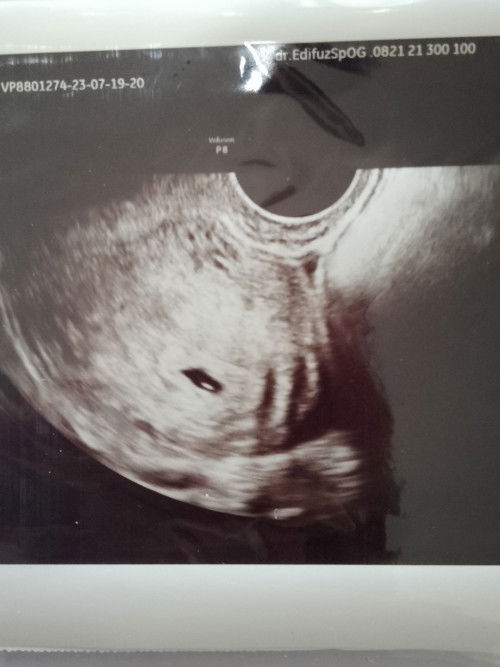

apakah sering merasakan sakit pinggang di usia kehamilan 5ming wajar ya bund? bner² bkin gk nyaman